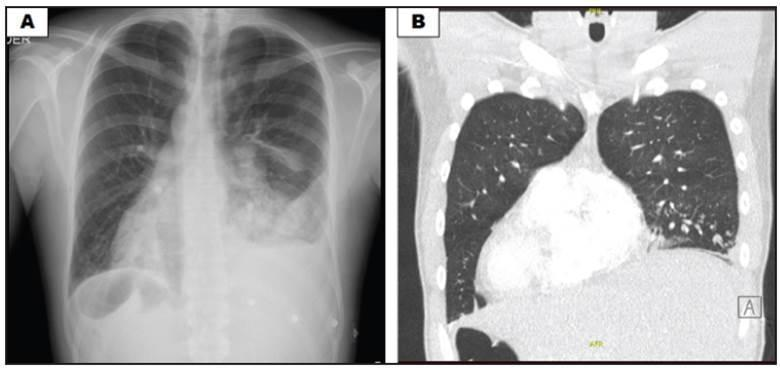

Синдрома Зиверта-Картагенера:

Рисунок А: рентгенограмма грудной клетки, показывающая альвеолярное затемнение в левой нижней доле, плевральный выпот и признаки потери объема, декстрокардией и правостороннее расположение пространства Траубе желудка.

Рисунок B: на томографии грудной клетки полное обратное расположение органов: сердце и желудок справа и печень слева.

1.Нормальное положение сердца и 2. декстрокардия